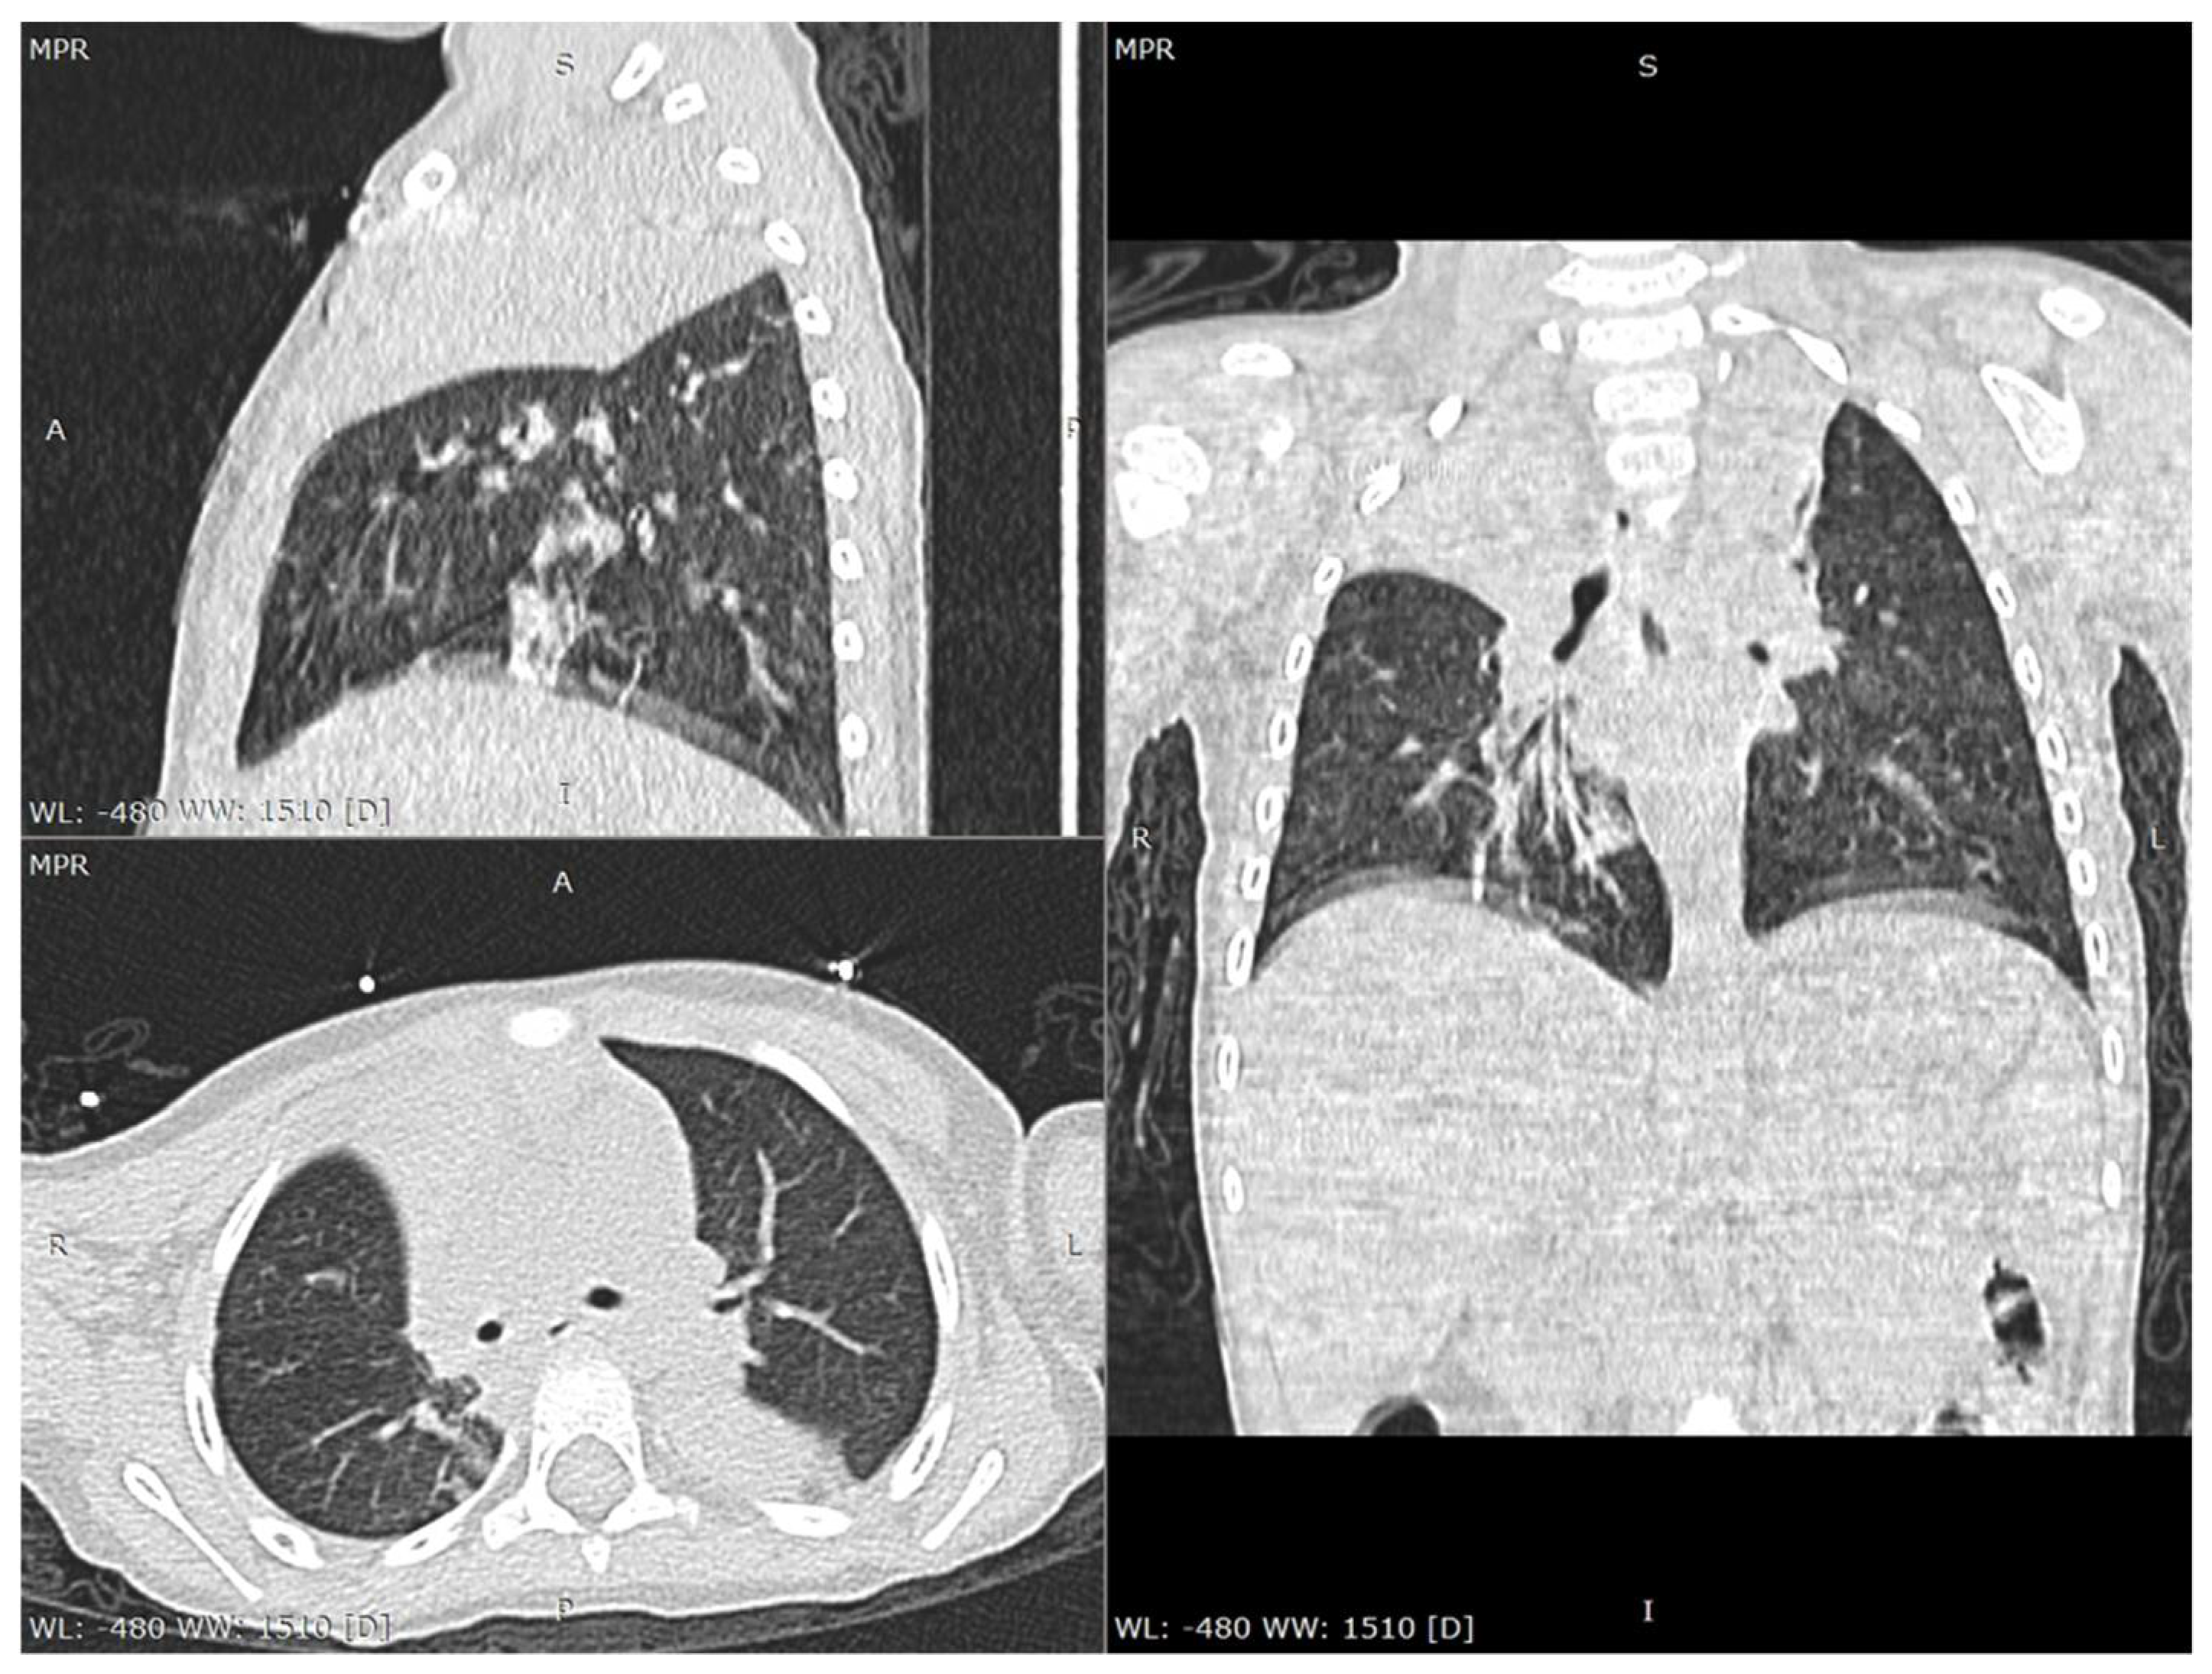

The laboratory tests performed on the day of admission revealed anemia (Hemoglobin—Hb 9.98 g/dL, Hematocrit—Htc 28.54%), a severely increased number of monocytes (9624/µL), and a mildly increased C-reactive protein (CRP 7 mg/L). Taking into account the family history, a real-time polymerase chain reaction (RT-PCR) of the oropharyngeal swab was performed and it tested positive for SARS-CoV-2. Moreover, both parents were confirmed with this infection. Both urine and blood cultures were negative. The serology for viral hepatitis B and C, as well as antinuclear and anti-double-strained DNA antibodies were negative. We performed a thoracic computed tomography (CT), which showed consolidation in the lower lobe of the left lung associated with an opacity in the right apex, suggesting possible atelectasis (Figure 1 and Figure 2). The cranial CT revealed no pathological findings. The patient was admitted to the intensive care unit with a diagnosis of COVID-19 in a severe form.

In spite of the fact that the lack of symptoms is relatively common in children, a wide spectrum of respiratory and digestive symptoms might be encountered in children with SARS-CoV-2, among which cough, pharyngeal erythema, fever, dyspnea, cyanosis, loss of appetite, diarrhea, gastrointestinal bleeding, abdominal pain, nausea or vomiting [8,14,15]. Nevertheless, according to the mother, our patient was completely asymptomatic before the seizures, in spite of the thoracic CT findings that definitely required a certain amount of time to appear. Laboratory parameters are usually unspecific for the diagnosis of SARS-CoV-2 infection, according to a review performed on 66 children, which revealed that 69.2% were found with a normal leukocyte count, 6% presented neutropenia, 4.6% neutrophilia, and 3% lymphopenia, while an increased CRP level was encountered in 13.6% of the cases [16]. The initial laboratory parameters in our cases showed only anemia, monocytosis, and a mildly increased C-reactive protein. Nevertheless, once the patient’s clinical course worsened, he developed leukopenia and neutropenia, along with hypoalbuminemia, also expressing mildly increased levels of ferritin and creatin kinase. Radiological findings might contribute to the diagnosis, revealing multilobar involvement, a peripheral distribution of lung lesions, consolidations with a surrounding halo and glass opacities, which are commonly seen on chest CT, and present in one-third of COVID-19 pediatric patients [14,17]. The chest CT performed in our case revealed consolidation within the inferior left lobe and an opacity in the right apex suggesting a multilobar involvement and peripheral distribution of the lesions.

Figure 1. Chest CT scan lung window: multiplanar reconstructions (axial, sagittal and coronal views) show atelectatic consolidation of the right upper lobe.

Figure 2. Chest CT scan lung window: multiplanar reconstructions (axial, sagittal and coronal views) also show atelectasis of several segments in the left lung (ventral segment from upper lobe, apical and posterior segments from lower lobe).